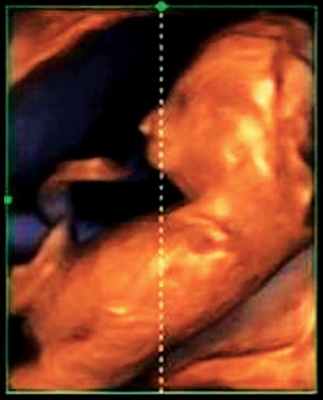

Использование трехмерного ультразвука, включая визуализацию поверхности, многоплоскостное и многослойное изображение, позволяет точно оценить различные черепно-лицевые структуры и их аномалии, включая расщелину неба (рис. 15, 16) и краниосиностоз. Изображения могут быть полезны для консультирования (рис. 17, 18). Использование 3D (рис. 19) может помочь дифференцировать закрытые и открытые швы. Использование 4D может быть использовано для оценки выражений лица.

Рисунок 19: Плод во втором триместре с краниосиностозом.

3D поверхностное изображение в скелетном режиме, аксиального вида черепа показывает сужение (стрелки) венечного шва (CS) и части переднего родничка (AF).